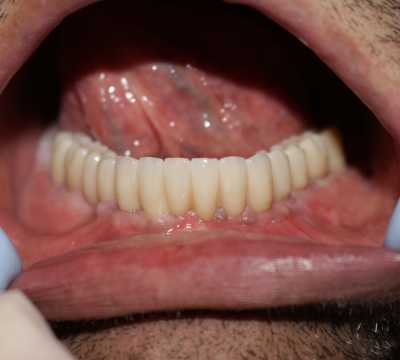

In cazul mandibulei au avut loc extractii, chiuretarea pungilor parodontale, inserarea postextractionala a 6 implanturi Paltop si s-a realizat in aceeasi zi o lucrare provizorie acrilica, cu care am restaurat functionalitatea aparatului dento maxilar urmand ca dupa 3 luni, dupa osteointegrarea finala a implanturilor sa concepem lucrarea finala.

Implantul Paltop oferă posibilitatea realizării unor lucrări cu o estetică impecabilă și o afectare minimă a țesuturilor la locul implantării. Profilul concav al bontului protetic ajută la formarea unui țesut gingival dens la nivelul legăturii transgingivale scăzând vizibilitatea bontului.